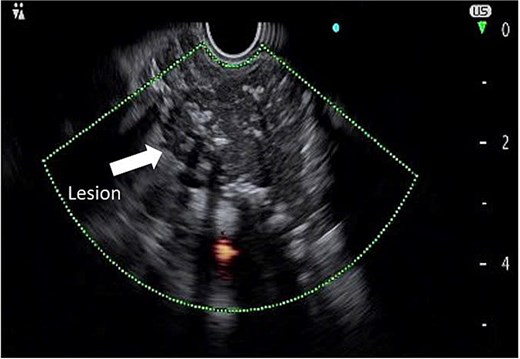

To further characterize the lesion, endoscopic ultrasound (EUS) was performed, which revealed a hypoechoic mass with clear margins, internal calcifications, and abundant vascularity (Fig. 2). A fine needle biopsy (FNB) using a 22G needle yielded multiple lymphoid cells, but the sample was insufficient for a definitive diagnosis. Given the inconclusive biopsy and persistent clinical suspicion of malignancy, surgical excision was planned.

Endoscopic ultrasound image demonstrating a hypoechoic mass with defined margins, internal calcifications, and increased vascular flow.